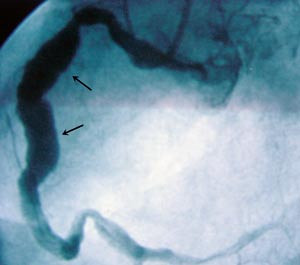

Pasienten ble henvist til regionsykehus med tanke på videre diagnostikk. Koronar angiografi viste ektatiske koronararterier uten signifikante stenoser (fig 3). MR av hjertet viste en solid rundaktig oppfylning på ca. 3,7 x 3,3 cm som lå like innenfor perikard, omringet av epikardialt fettvev. Største del av oppfylningen buket inn mot høyre atrium og hadde nær relasjon til tricuspidalklaffen og proksimale del av høyre ventrikkel. Den tentative diagnosen etter disse tilleggsundersøkelsene var hjertetumor eller aneurisme i en av koronararteriene.

Funn av patologiske strukturer i furen mellom høyre atrium og høyre ventrikkel ved ekkokardiografi bør gi mistanke om aneurisme i høyre koronararterie. Mistanken om at vår pasient kunne ha et slikt aneurisme, ble forsterket etter at koronarangiografi viste ektatiske koronarkar, siden aneurismer og ektasier ofte foreligger samtidig.